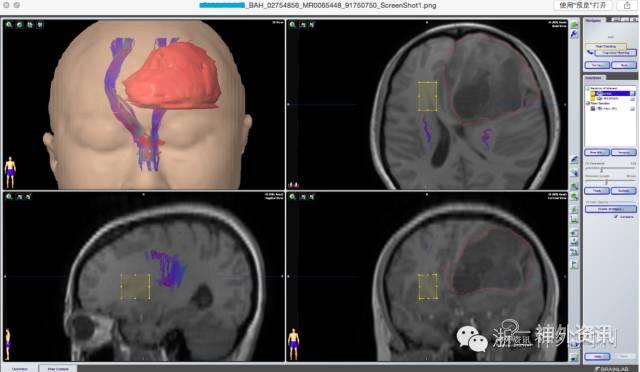

图3. 术前3.0T磁共振显示左侧额叶巨大占位,利用Brainlab手术计划系统iPlan,勾画肿瘤大致边界,融合DTI显示传导束向后侧贴近肿瘤并有移位,左右连接的胼胝体神经纤维明显右移。